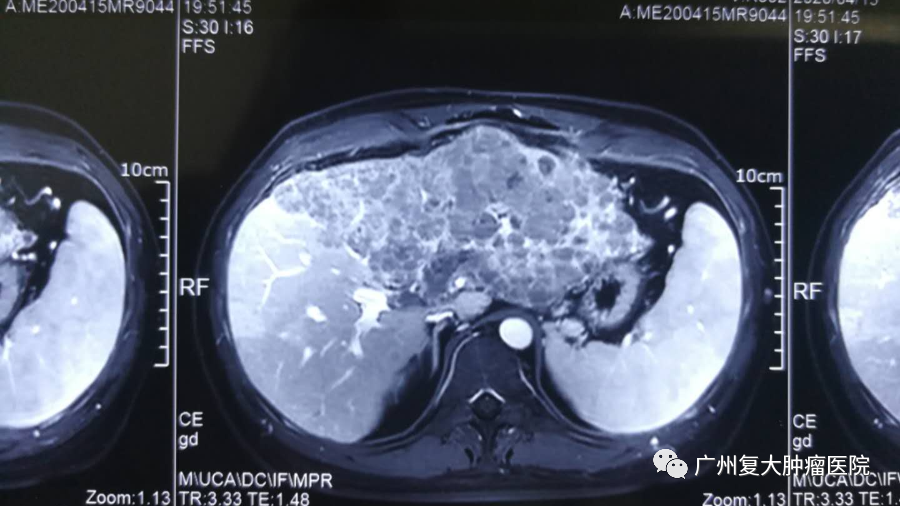

李先生去年1月份因腹胀不适,伴有发热的症状,到当地医院检查发现原发性巨块型肝癌。由于肿瘤从14公分疯长到20公分左右,且巨大无法手术切除,李先生选择来到广州复大就诊。为进一步降低肿瘤负荷,提高生活质量,改善生存期,李先生在我院接受几次介入治疗后,情况得到基本控制,绝大部分肿瘤已经坏死。

治疗前

治疗后

介入科杨清峰主任表示患者来院时肝左叶全是肿瘤,甲胎蛋白指数高达8872IU/ml。而介入治疗属于微创技术,创伤小,效果明显。它是通过皮下置入动脉泵或者直接经导管将化疗药物注入肿瘤的供血动脉,以提高药物在肿瘤内的浓度,从而获得更好的肿瘤反应,同时降低化疗药物在体循环中的浓度,减少对其脏器的毒副作用。通过介入化疗达到降期目的,为根治性手术创造条件,这对于不适合手术的患者来说是一种新的选择。